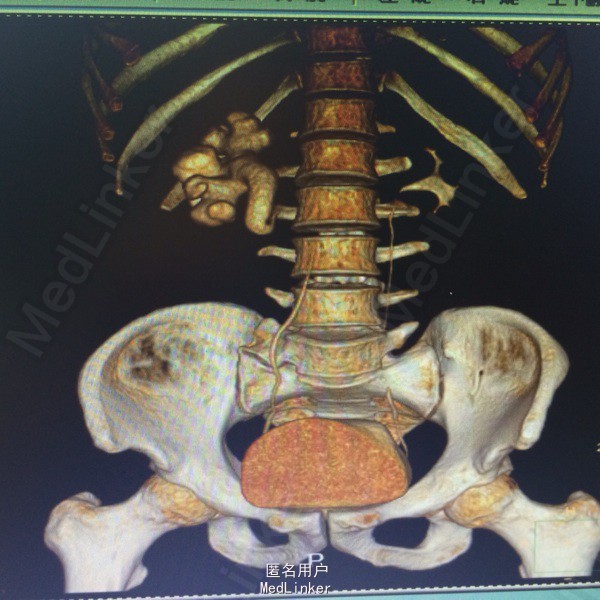

入院后查体,T 36.7℃,P 73次/分,R 21次/分, BP 130/90mmHg。全腹无压痛,反跳痛。右侧胆囊压痛点无压痛反跳痛。右侧腰部叩击痛阳性。右侧输尿管走形区无压痛叩击痛。外生殖器未见异常。 各项生化指标检验在正常范围,尿常规 RBC 阴性,WBC 阴性。泌尿系CTU检查:右肾肾盂及输尿管上段扩张积水,输尿管中段局部走形异常,中下段无明显扩张。左侧肾盂肾盏及输尿管未见明显异常密度影。膀胱充盈良好,未见异常密度影。增强:右侧输尿管上段局部弯折,弯折处狭窄,未走行于腰大肌前方,自下腔静脉后方向左侧,再向前走形。下段走行正常。左侧输尿管未见明显异常密度影。左肾未见明显异常密度影,右肾实质内可见一小圆形低密度影,无明显强化。诊断意见:右输尿管上段弯曲并走行异常,并上段输尿管扩张积水。右肾盂扩张积水,结合临床评估。2右肾小囊肿。

术前诊断:腔静脉后输尿管 处理:腹腔镜下右侧肾盂成形术,术中游离出扩张积水的肾盂及输尿管上段,在肾盂输尿管连接部离断。分离出下腔静脉后,将腔静脉后端走形的输尿管游离出,并游离整个输尿管至髂血管交叉处。将受压段的输尿管截断,修剪扩张的肾盂及输尿管,与游离的远端输尿管vy吻合成形,期间置入6F D-J管。术后5天拔除肾周引流管,留置尿管6天。